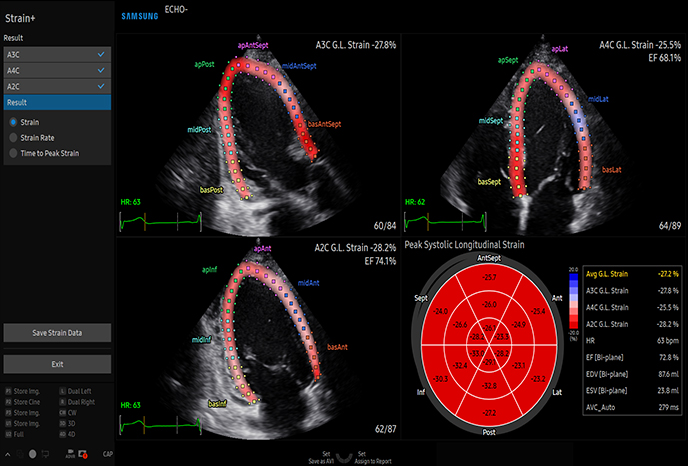

변형률 영상

자동 EF(박출률) 계산